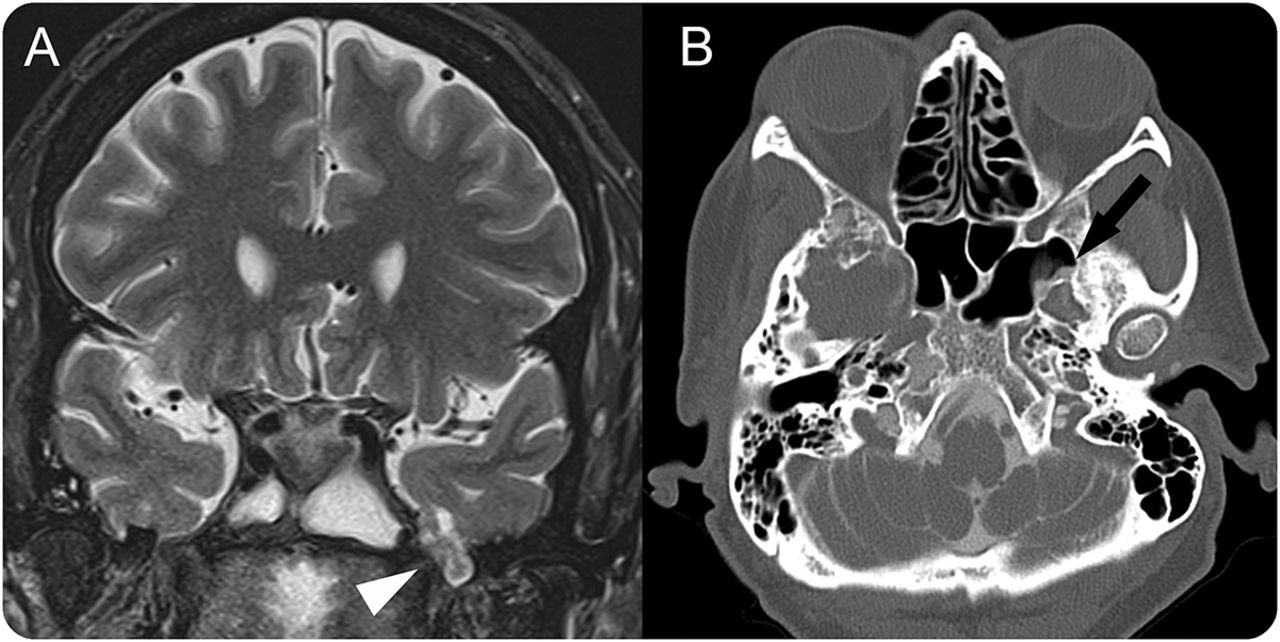

一个63岁的女人,癫痫和慢性头痛被癫痫持续状态。腰椎穿刺显示开启压力的增加320毫米H2O和细菌性脑膜炎。MRI大脑表现出偏空鞍,曲折的视神经鞘,压扁的视神经乳头状突起,和许多著名的蛛网膜颗粒,符合慢性特发性颅内高血压(IIH),以及明亮的脑脊液信号和脑实质内左meningoencephalocele (图,一个)。CT cisternogram确认沟通的蛛网膜下腔meningoencephalocele左蝶窦通过小骨性缺陷(图B)。虽然大多数CSF泄漏有关创伤,颅内高压症越来越被认为是一个自发的泄露的原因。1,2而开启压力的增加可能是由于她的急性脑膜炎,她头痛症状,MRI发现暗示长期颅内高血压。监控和颅内高压症必须伴随医疗手术修复,避免复发。2

MRI和CT cisternogram

(A)冠T2 MRI显示双边meningoencephaloceles患疝气的左侧颞叶及周边CSF(箭头)。(B) CT cisternogram显示囊内的对比扩展通过一个点状的骨性缺陷在横向方面的左侧蝶窦与脑脊液漏的网站一致(箭头所指)。